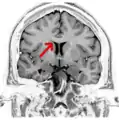

مقطع تاجي، التصوير بالرنين المغناطيسي للدماغ على مستوى نواة المذنب لتأكيد الجسم الثفني